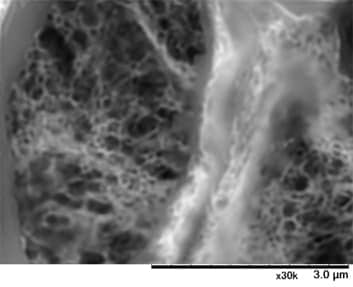

腎生検標本のTEM像

左:Alport 症候群、右:菲薄基底膜病

画像比較のため、ここでは両症例共にTEM像を示しています。